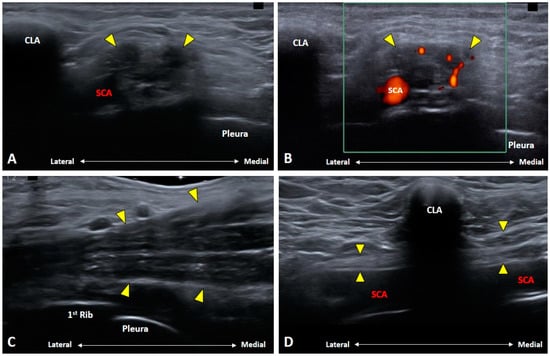

3.5. Which Vascular Structure(s) Should We Be Aware Of?